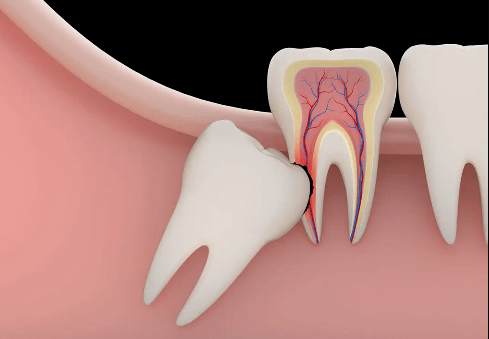

智齿牙图片神经

智齿离神经很近拔牙如果伤到神经有多严重

智齿和下牙槽神经的毗邻关系虽然拔智齿存在风险,但是选择正规的口腔

阻生齿最常见于下颌第三磨牙,俗称智齿,此牙萌出年龄在18岁前后,由于

将前面的好牙顶坏,继而出现龋齿,牙齿松动的症状.1,智齿有什么危害?

下图绿色的是舌神经,它走形基本紧挨智齿的牙根部,被损伤会引起舌部的